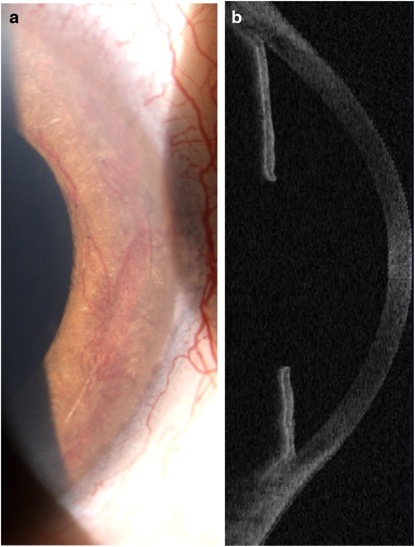

2014 年 10 月,患者于血透时出现严重的眼痛和视力下降,IOP 右眼 38 mmHg,左眼 34 mmHg,立即予 Cosopt(主要成分为多佐胺和噻吗洛尔)及苏为坦(曲伏前列素)滴眼液滴眼。眼科检查,右眼最佳矫正视力(BCVA)2/20,左眼无视力。眼前节检查示虹膜红变(图 1a),房角镜显示新生血管覆盖虹膜角膜角,鼻侧及颞侧小梁网水平发生虹膜前粘连,OCT 表现为「假房角」(图 1b)。

图 1 a 为生物显微镜示虹膜新生血管;b 为眼前节 OCT 示房角完全关闭